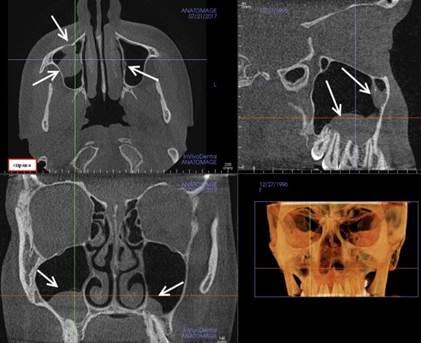

Рис. 2. Компьютерная томограмма пациента. Стрелками указаны объемные образования в обеих верхнечелюстных пазухах.

При искривлении носовой перегородки вбок у пациентов с объемными образованиями в гайморовых пазухах с обеих сторон были выявлены большие воздушные буллы средней носовой раковины.

Рис. 4. Компьютерная томограмма пациента. Стрелками указаны большие воздушные буллы средних носовых раковин.